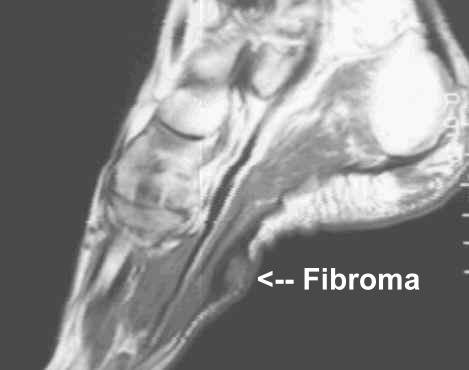

Within the arch of the foot, firm, nodular masses may form. These can occur as a single mass or in clusters. They are called plantar fibromas and are a non-cancerous tumor that forms within a ligament in the arch of the foot called the plantar fascia. Frequently, they will slowly enlarge causing pain while walking. Their cause cannot always be determined. Damage to the tendon will cause their occurrence and there is an association with taking the drug Dilantin. In 10% of the cases, patients will also demonstrate similar lumps in the palms of the hands called Dupuytren’s Contracture.